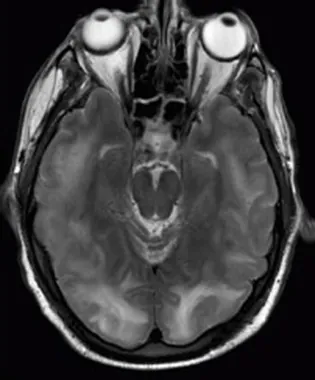

M R I scan of a brain with specific tumors.

Figure 1.5 These two applications of physics have more in common than meets the eye. Microwave ovens use electromagnetic waves to heat food. Magnetic resonance imaging (MRI) also uses electromagnetic waves to yield an image of the brain, from which the exact location of tumors can be determined. (credit: Rashmi Chawla, Daniel Smith, and Paul E. Marik)